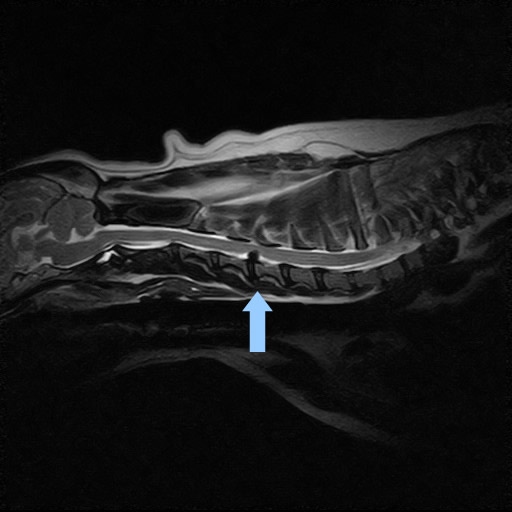

症例① 頚部椎間板ヘルニア

首を触ると痛がる、下を向いていると来院

| 頭部・頚部MRI検査 | 頚部椎間板ヘルニア |

| 診断 | 頚部椎間板ヘルニア (グレードⅡ) |

| 治療 | ステロイドによる内科的治療をおこなったが、痛みが完全にはなくならないため外科的治療をおこない完治 |

![]() 頚部MRI検査 矢印が飛び出した椎間板 下から上に 飛び出して上にある脊髄神経を圧迫 |